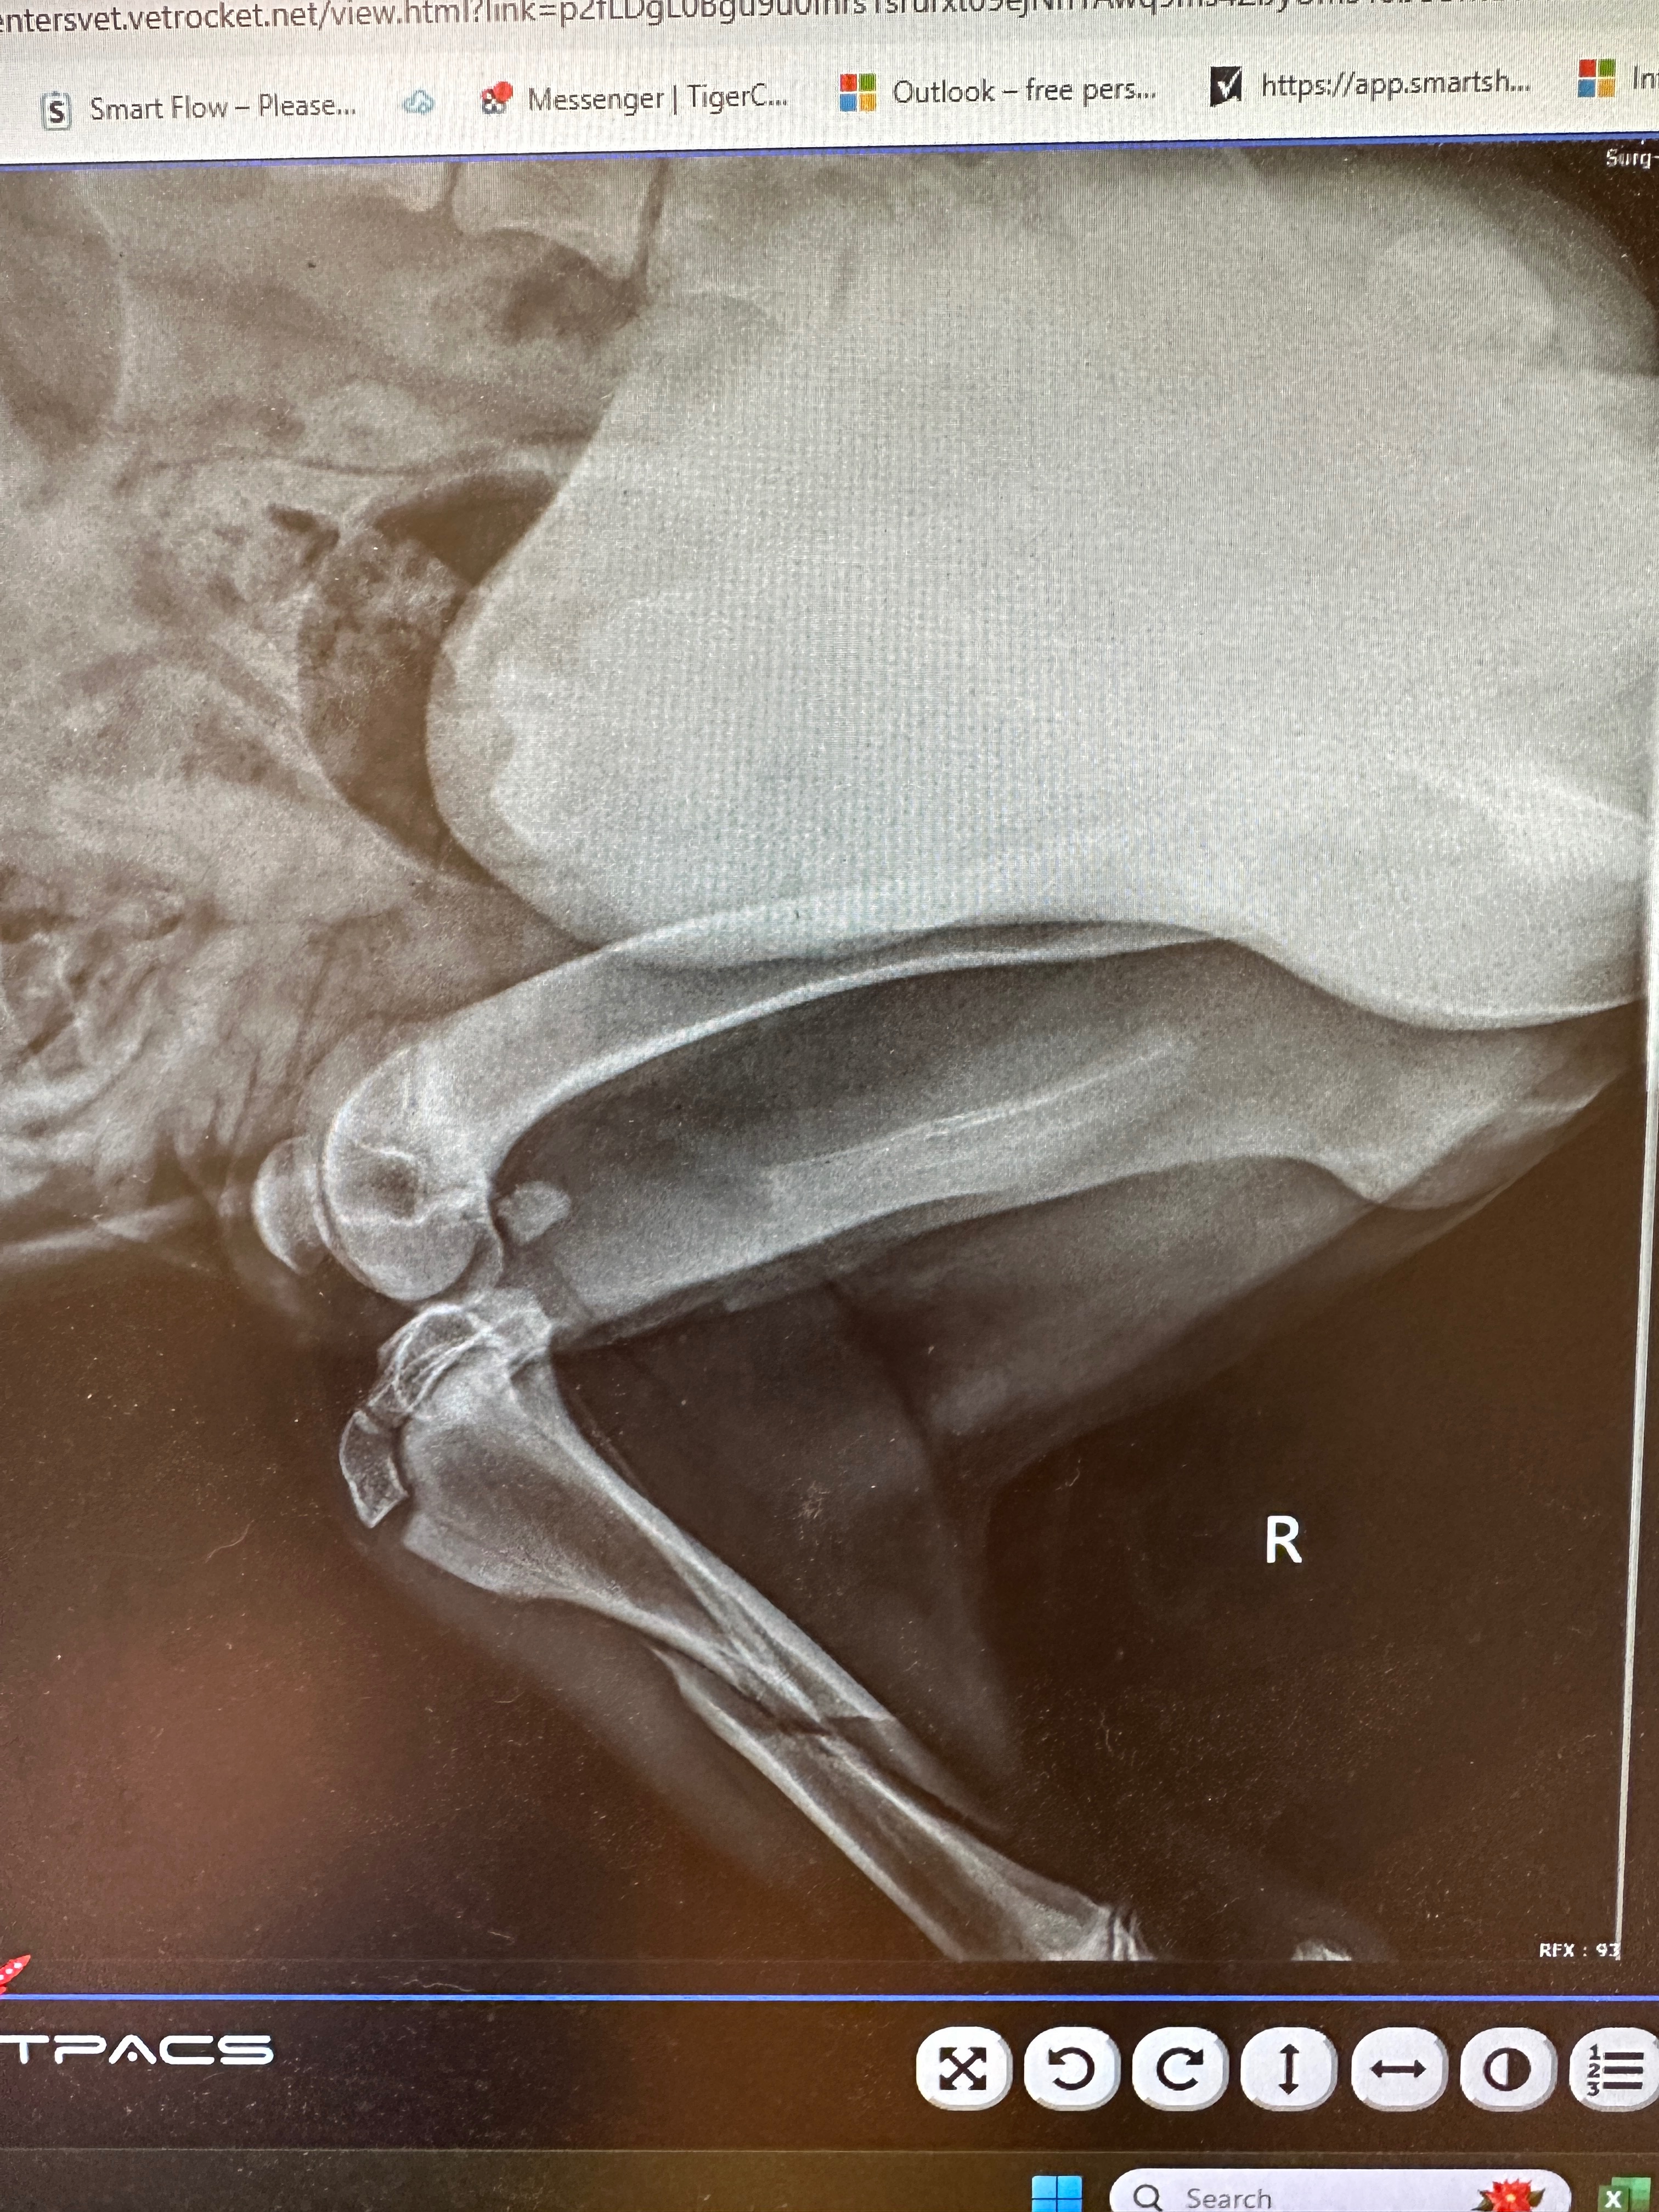

On Friday, December 12th, after returning home from a Christmas party, we took Ozzy out for a short walk before bed. The night started out perfectly normal—Ozzy was his usual playful self, jumping around and tugging at his leash. Suddenly, as he leapt, he let out the most heartbreaking cry we’ve ever heard. We rushed to restrain him and immediately took him to the pet hospital, where we learned he had broken his leg. The news was devastating, and we were told he needs surgery to repair the fractures so he can continue to grow healthy and strong.

On Friday, December 12th, after returning home from a Christmas party, we took Ozzy out for a short walk before bed. The night started out perfectly normal—Ozzy was his usual playful self, jumping around and tugging at his leash. Suddenly, as he leapt, he let out the most heartbreaking cry we’ve ever heard. We rushed to restrain him and immediately took him to the pet hospital, where we learned he had broken his leg. The news was devastating, and we were told he needs surgery to repair the fractures so he can continue to grow healthy and strong.